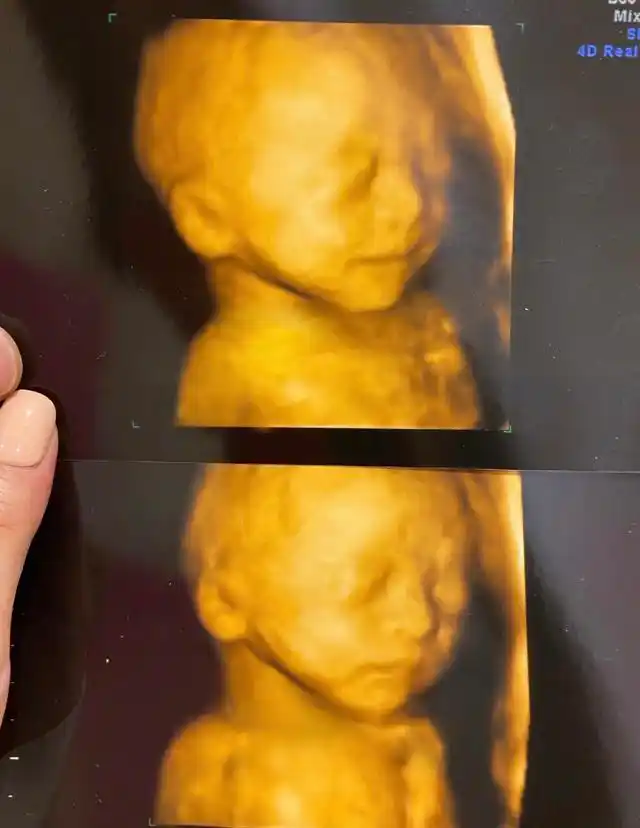

四维拍出来,当时一看好丑啊,这鼻子也太大了,我的显性基因也太强了

怀孕6个月宝宝四维拍照嘴巴和鼻子都好大生出来后是不是很丑

四维通过,大眼睛高鼻梁酒窝女宝接走